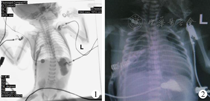

南京医科大学附属儿童医院胸心外科2017年1月至2019年6月间共完成食道闭锁手术46例,其中Ⅲ型食管闭锁矫治术后出现吻合口漏患儿17例。包括,男14例,女3例;年龄1 d至5个月,中位年龄3 d;体重1.6~6.0 kg,中位体重4.2 kg。所有患儿均在术后出现胸腔引流增多、发热、血象升高等症状,胸部X线片检查可见不同程度的气胸、液胸,口服美蓝后胸腔引流管中有蓝色液体引出或食管造影明确显示食管胸膜漏(图1)。所有患儿一经诊断立即给予胸腔稀碘伏、生理盐水交替冲洗引流,并注意保持引流通畅(图2)。依据药敏结果选用敏感抗生素,积极营养支持,加强呼吸道护理,定期复查消化道造影或食管镜检查。

术后前3 d每天复查胸部X线,此后每周复查1次X线以确定支架是否发生移位(图7)。支架置入术后4周回收牵引线将支架从口腔取出,复查食管镜,观察漏口生长情况。

覆膜支架置入手术时间为30~80 min,平均55 min。术后6例患儿监护室滞留时间<24 h;另1例因合并室间隔缺损术后无法撤离呼吸机,5 d后家属放弃治疗。6例患儿术后撤离呼吸机6 h后即可恢复经口流质饮食或鼻饲流质饮食,术后2~4 d恢复经口饮食。术后住院时间为2~4周,6例患儿复查无支架移位等并发症,于术后4周取出支架,复查消化道造影及胃镜检查见漏口愈合(图8)。取支架术中胃镜检查可见支架远端食管黏膜略增厚,1个月后再次复查胃镜或消化道造影可见黏膜增厚消失。部分患儿原漏口处呈小憩室样改变,但随着随访时间的延长,小憩室逐渐消失。